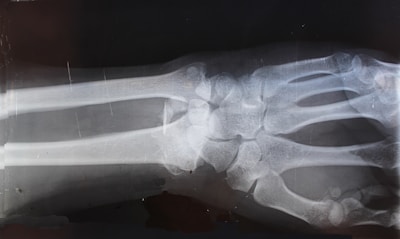

x-ray result